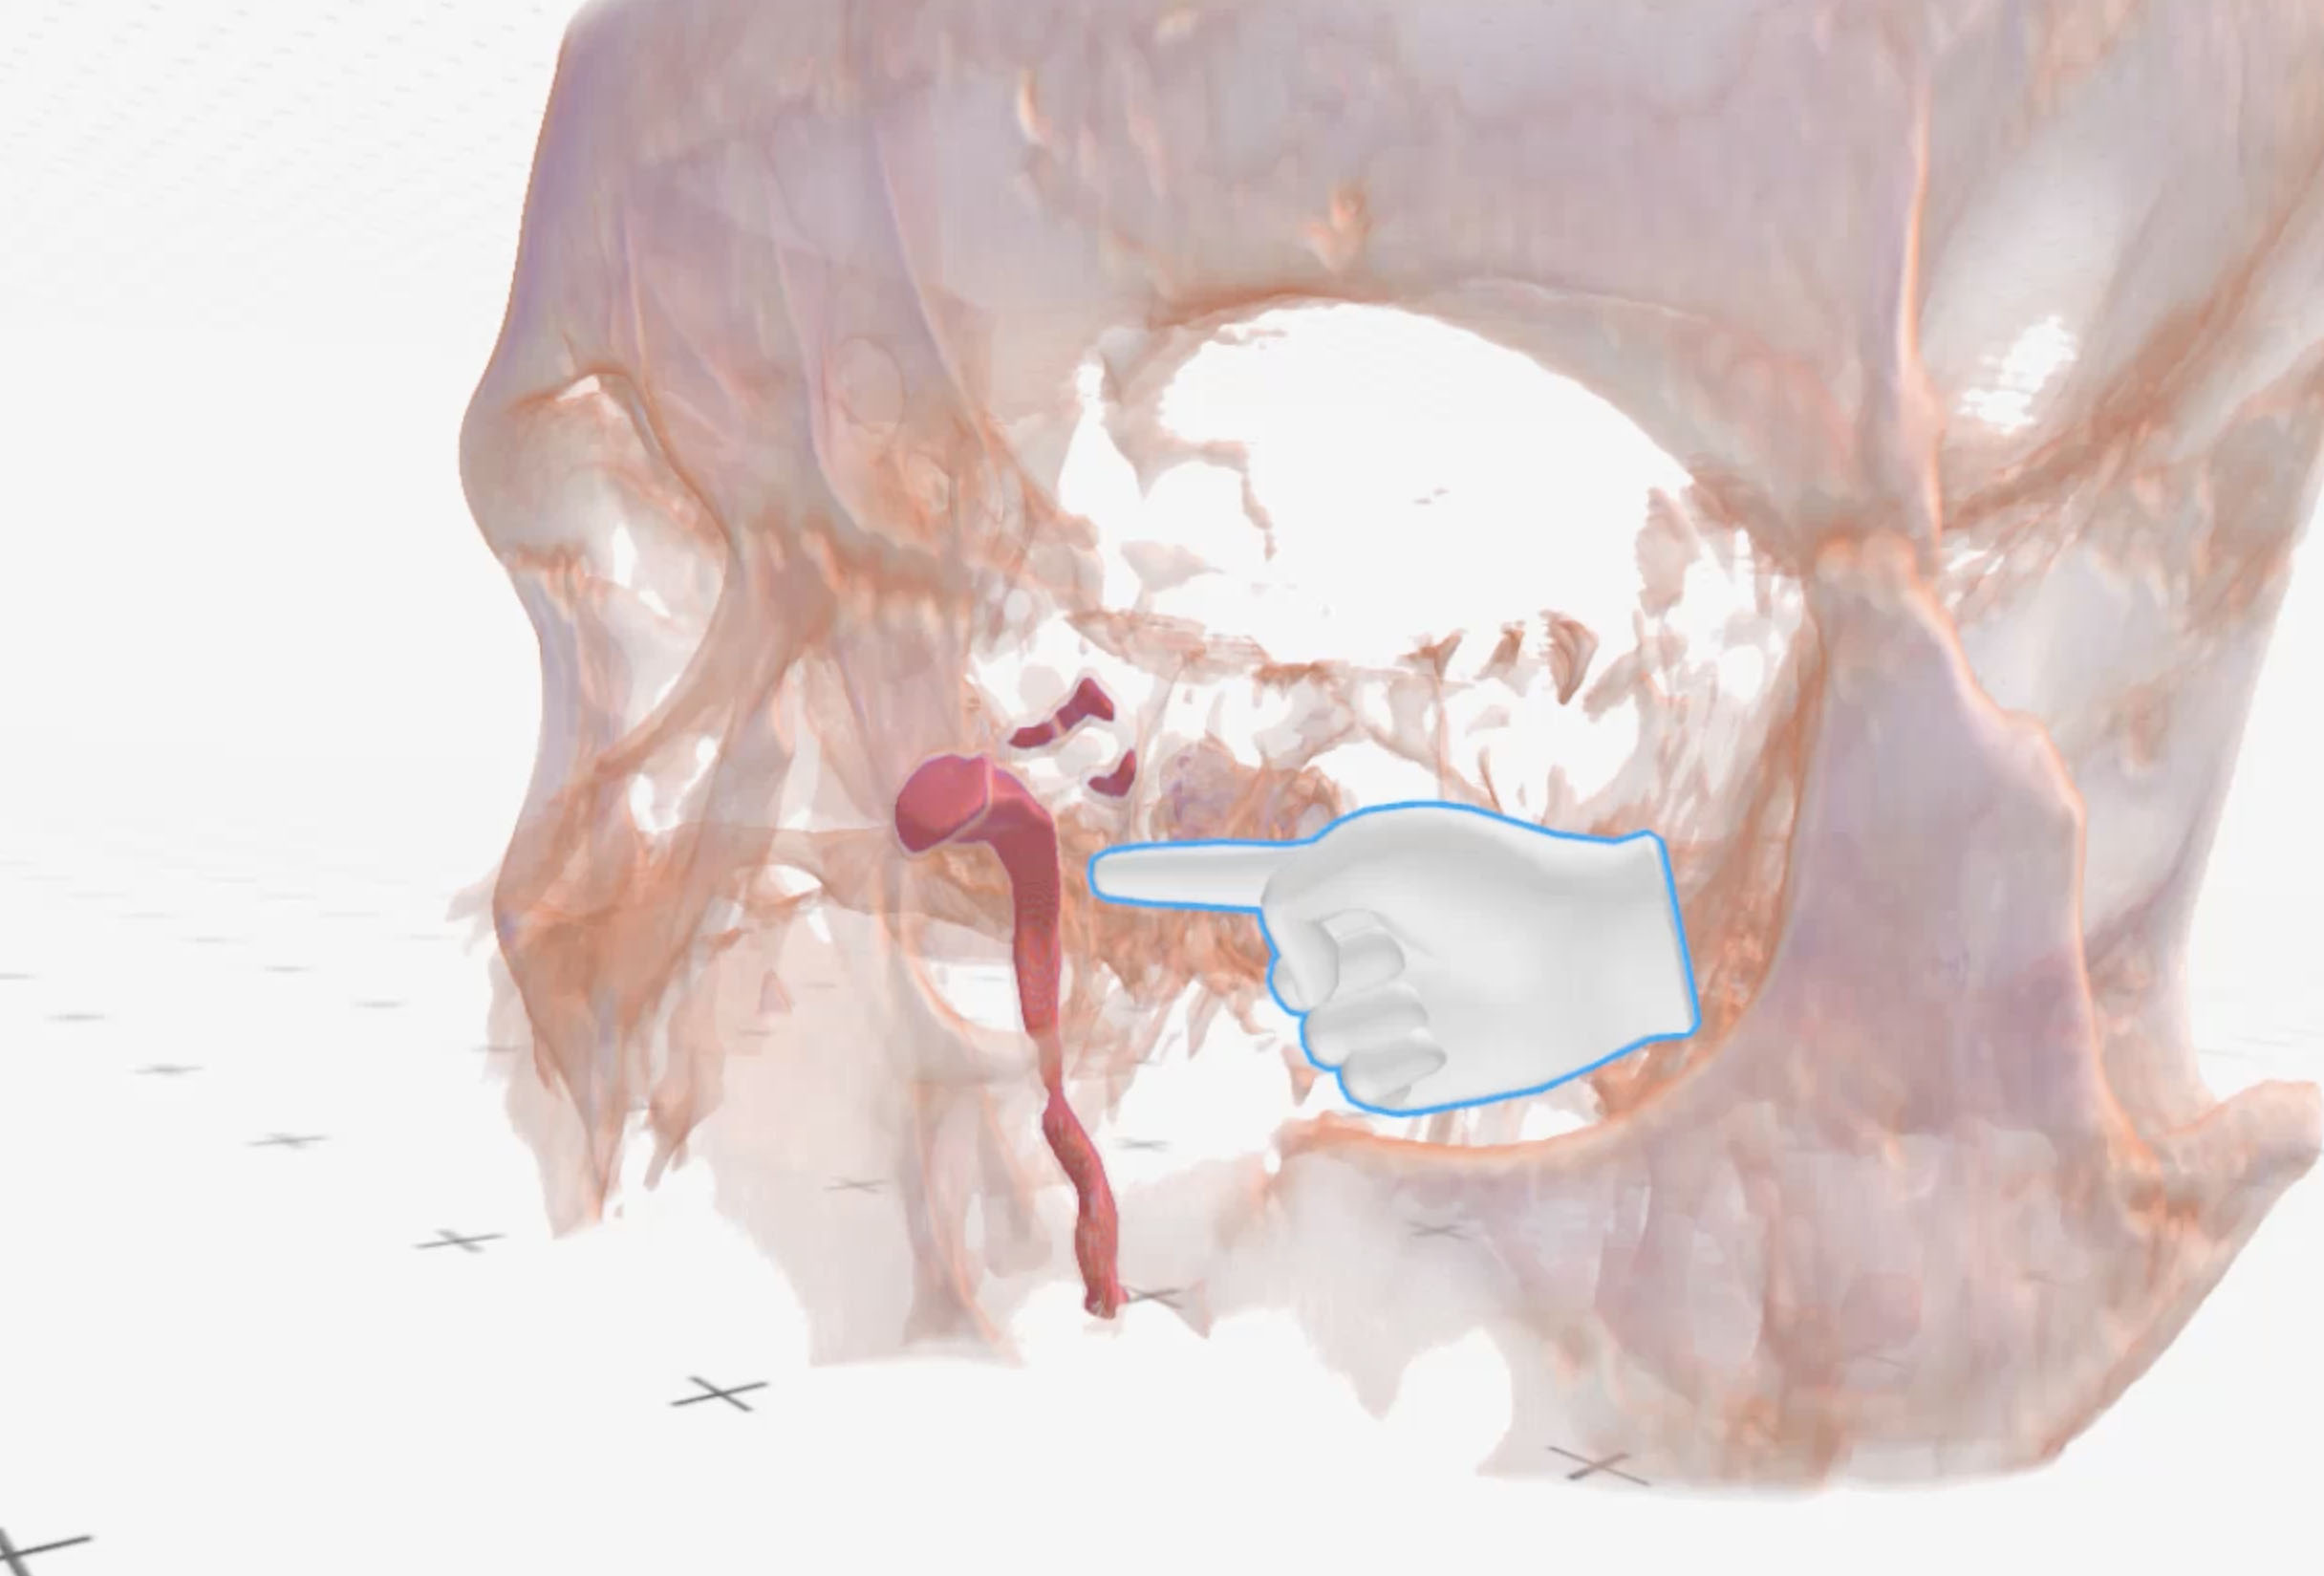

Medical Imaging XR (Medicalholodeck AG, Zurich, Switzerland) three-dimensional reconstructions obtained from CT-DCG DICOM files showed a well-defined lesion in the left lacrimal sac fossa, extending up to the beginning of the nasolacrimal canal (bony). The lacrimal sac appeared to be compressed against the posterior wall of the lacrimal fossa (Fig. 2-4).

Figure 3. Medical Imaging XR reconstruction shows isolated contrast dye in the left lacrimal passages (red) and significantly compressed lacrimal sac